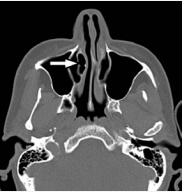

A coronal section computerized tomography (CT) scans showed pneumatized right inferior concha and an air-filled sac in the pneumatized inferior concha associated with the right maxillary sinus (Figure 1).

The coronal CT image of the right inferior concha bullosa communicating into the right maxillary sinus.

Figure 1: The coronal CT image of the right inferior concha bullosa communicating into the right maxillary sinus.